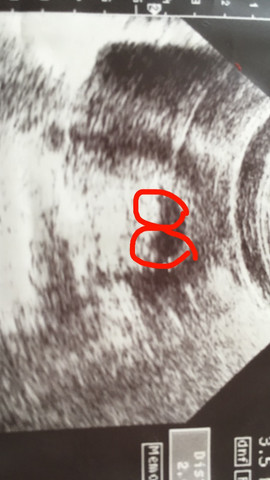

Zwillinge 9 SSW Hallo liebe Experten, ich bin heute bei rechnerisch und wir waren beim Ultraschall Man konnte beide Fruchthöhle mit den Babys sehen (zweieiig, jedes isst vom eigenem Tellerchen meinte die Ärztin) Beide Herzen schlagen und sie sind gleich Eineiige Zwillinge werden in der Medizin auch monozygote Zwillinge genannt. ⭐️Willkommen im 3 Monat Deiner Schwangerschaft In der 9 SSW haben sich alle Organe des kleinen Fötus vollständig gebildet Er bewegt bereits seine Arme und Beine Unglaublich, oder?. Links noch der Querschnitt des Abdomens mit angeschnittener Magenblase 19 SSW SIAMESISCHE ZWILLINGE / 10 Schwangerschaftswoche B ild 601 Bild 602 Bilder 601 und 602 zeigen die seltene Erkrankung der unvollständigen Teilung eineiiger Zwillinge in der 10 SSW Diese 2 Feten sind am Rumpf zusammen gewachsen.

SSW einen Ultraschall macht In dieser Zeitspanne kann der Gynäkologe wahrscheinlich erkennen, ob die Babys in zwei getrennten oder einer gemeinsamen Embryonalhülle heranwachsen Auch das Vorhandensein nur einer gemeinsamen Plazenta deutet eindeutig auf eineiige Zwillinge hin. Woche (SSW11) « Letzter Zwillinge im 3 Monat (SSW 9) Weitere interessante Themen 11 SchwangerschaftsWoche (SSW 10) In der 11 Schwangerschaftswoche bildet sich das Geschlecht Ihres Babys Im Video erfahren Sie, warum Sie jetzt mit Schlafproblemen zu kämpfen haben. Frühe Zwillingsschwangerschaften im Ultraschall Eineiige Zwillinge in der 55 Schwangerschaftswoche Schwangerschaften entstehen und das ist nun wirklich nicht überraschend neu nachdem eine Eizelle von einem Samenfaden befruchtet wurde Zwillinge können auf zwei Arten entstehen 8 SSW Ultraschall Das ist zu sehen.